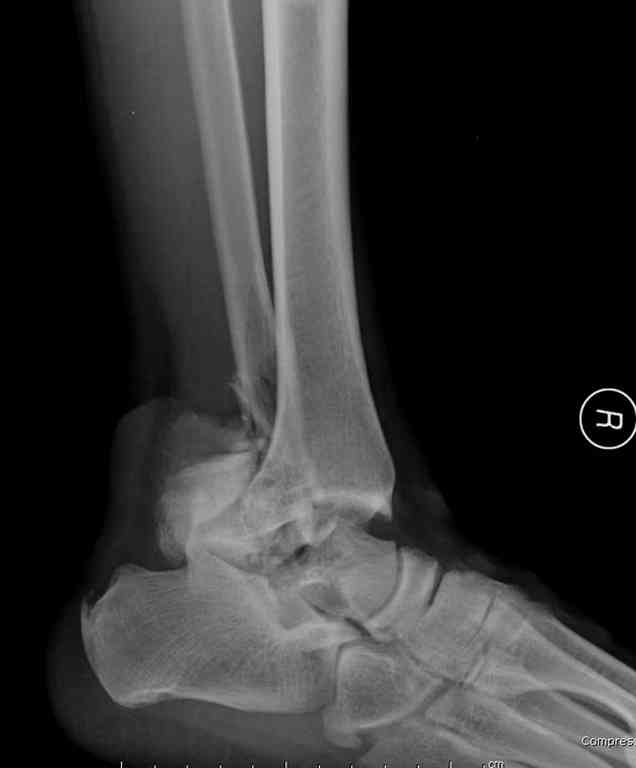

10 дней назад поступил с открытым повреждением медиальной лодыжки и переломо вывихом таранной кости. Ургентно сделана репозиция с наложением наружного фиксатора + Irrigation&Debridment.

Во время репозиции выявили повреждение заднего сухожилия м. тибиалис и задней большеберцовой артерии. Медиальную рану удалось закрыть частично и установлен вакуум.

Вчера провели фиксацию.

Из-за многооскольчатости дистальной части малоберцовой, где невозможно было провести фиксацию шурупами, перелом зафиксирован подпирающей пластиной, которая должна служить дополнением отсутствующей дистальной части малоберцовой (lateral cortex substitute).

Для стабильности два шурупа на синдесмоз.

Медиальную рану с приближенными краями продолжаем вакуумировать (KCI). Наружный фиксатор оставлен на пару недель, надеюсь, небольшая рана будет гранулировать и закроется без кожной пластики. Фиксация медиальной ложыжки не планируется.